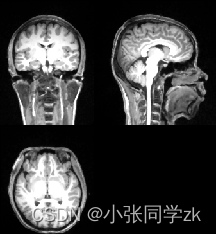

通过使用ITK中的itk::StripTsImageFilter类来实现分割功能,该类属于复合过滤器。在输入MRI图像的同时输入脑掩膜图像atlasImage.mha和atlasMask.mha,如图2.8.27所示:

图2.8.27 脑核磁图像和脑掩膜图像 [19]